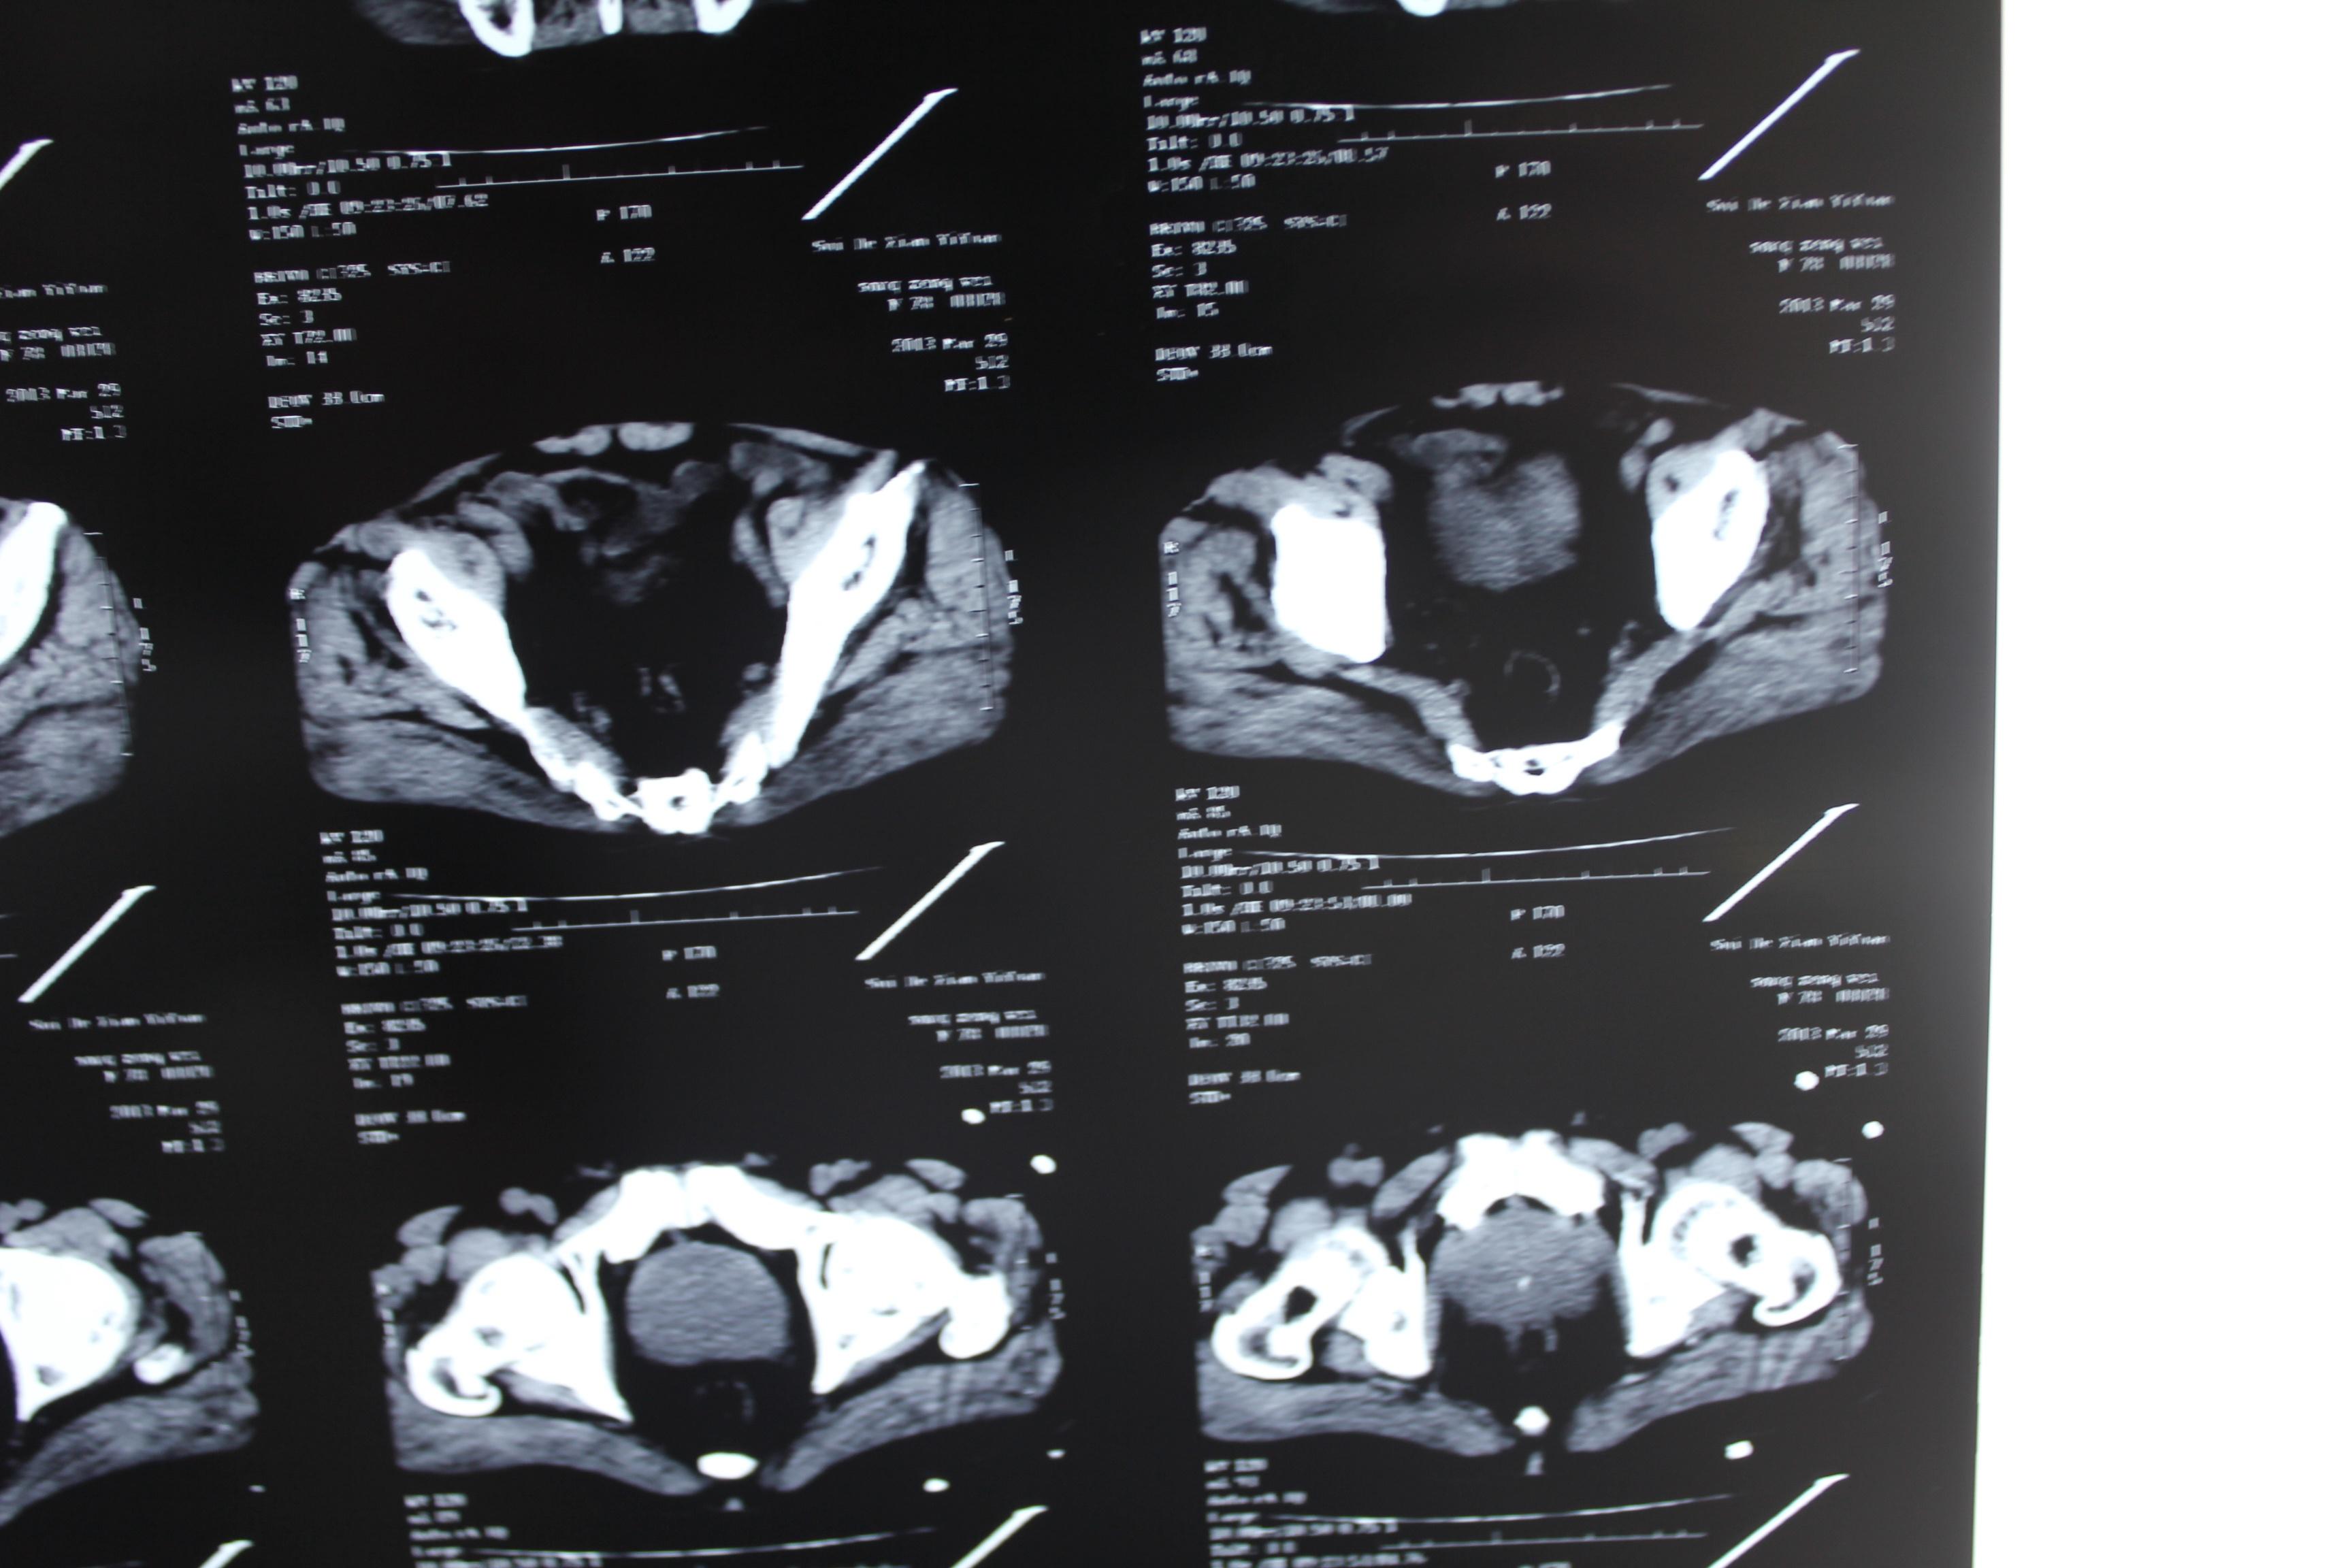

老年患者78岁,反复腰背部溃烂流脓4年,既往30年前曾在包块处排出蛔虫一条。CT: